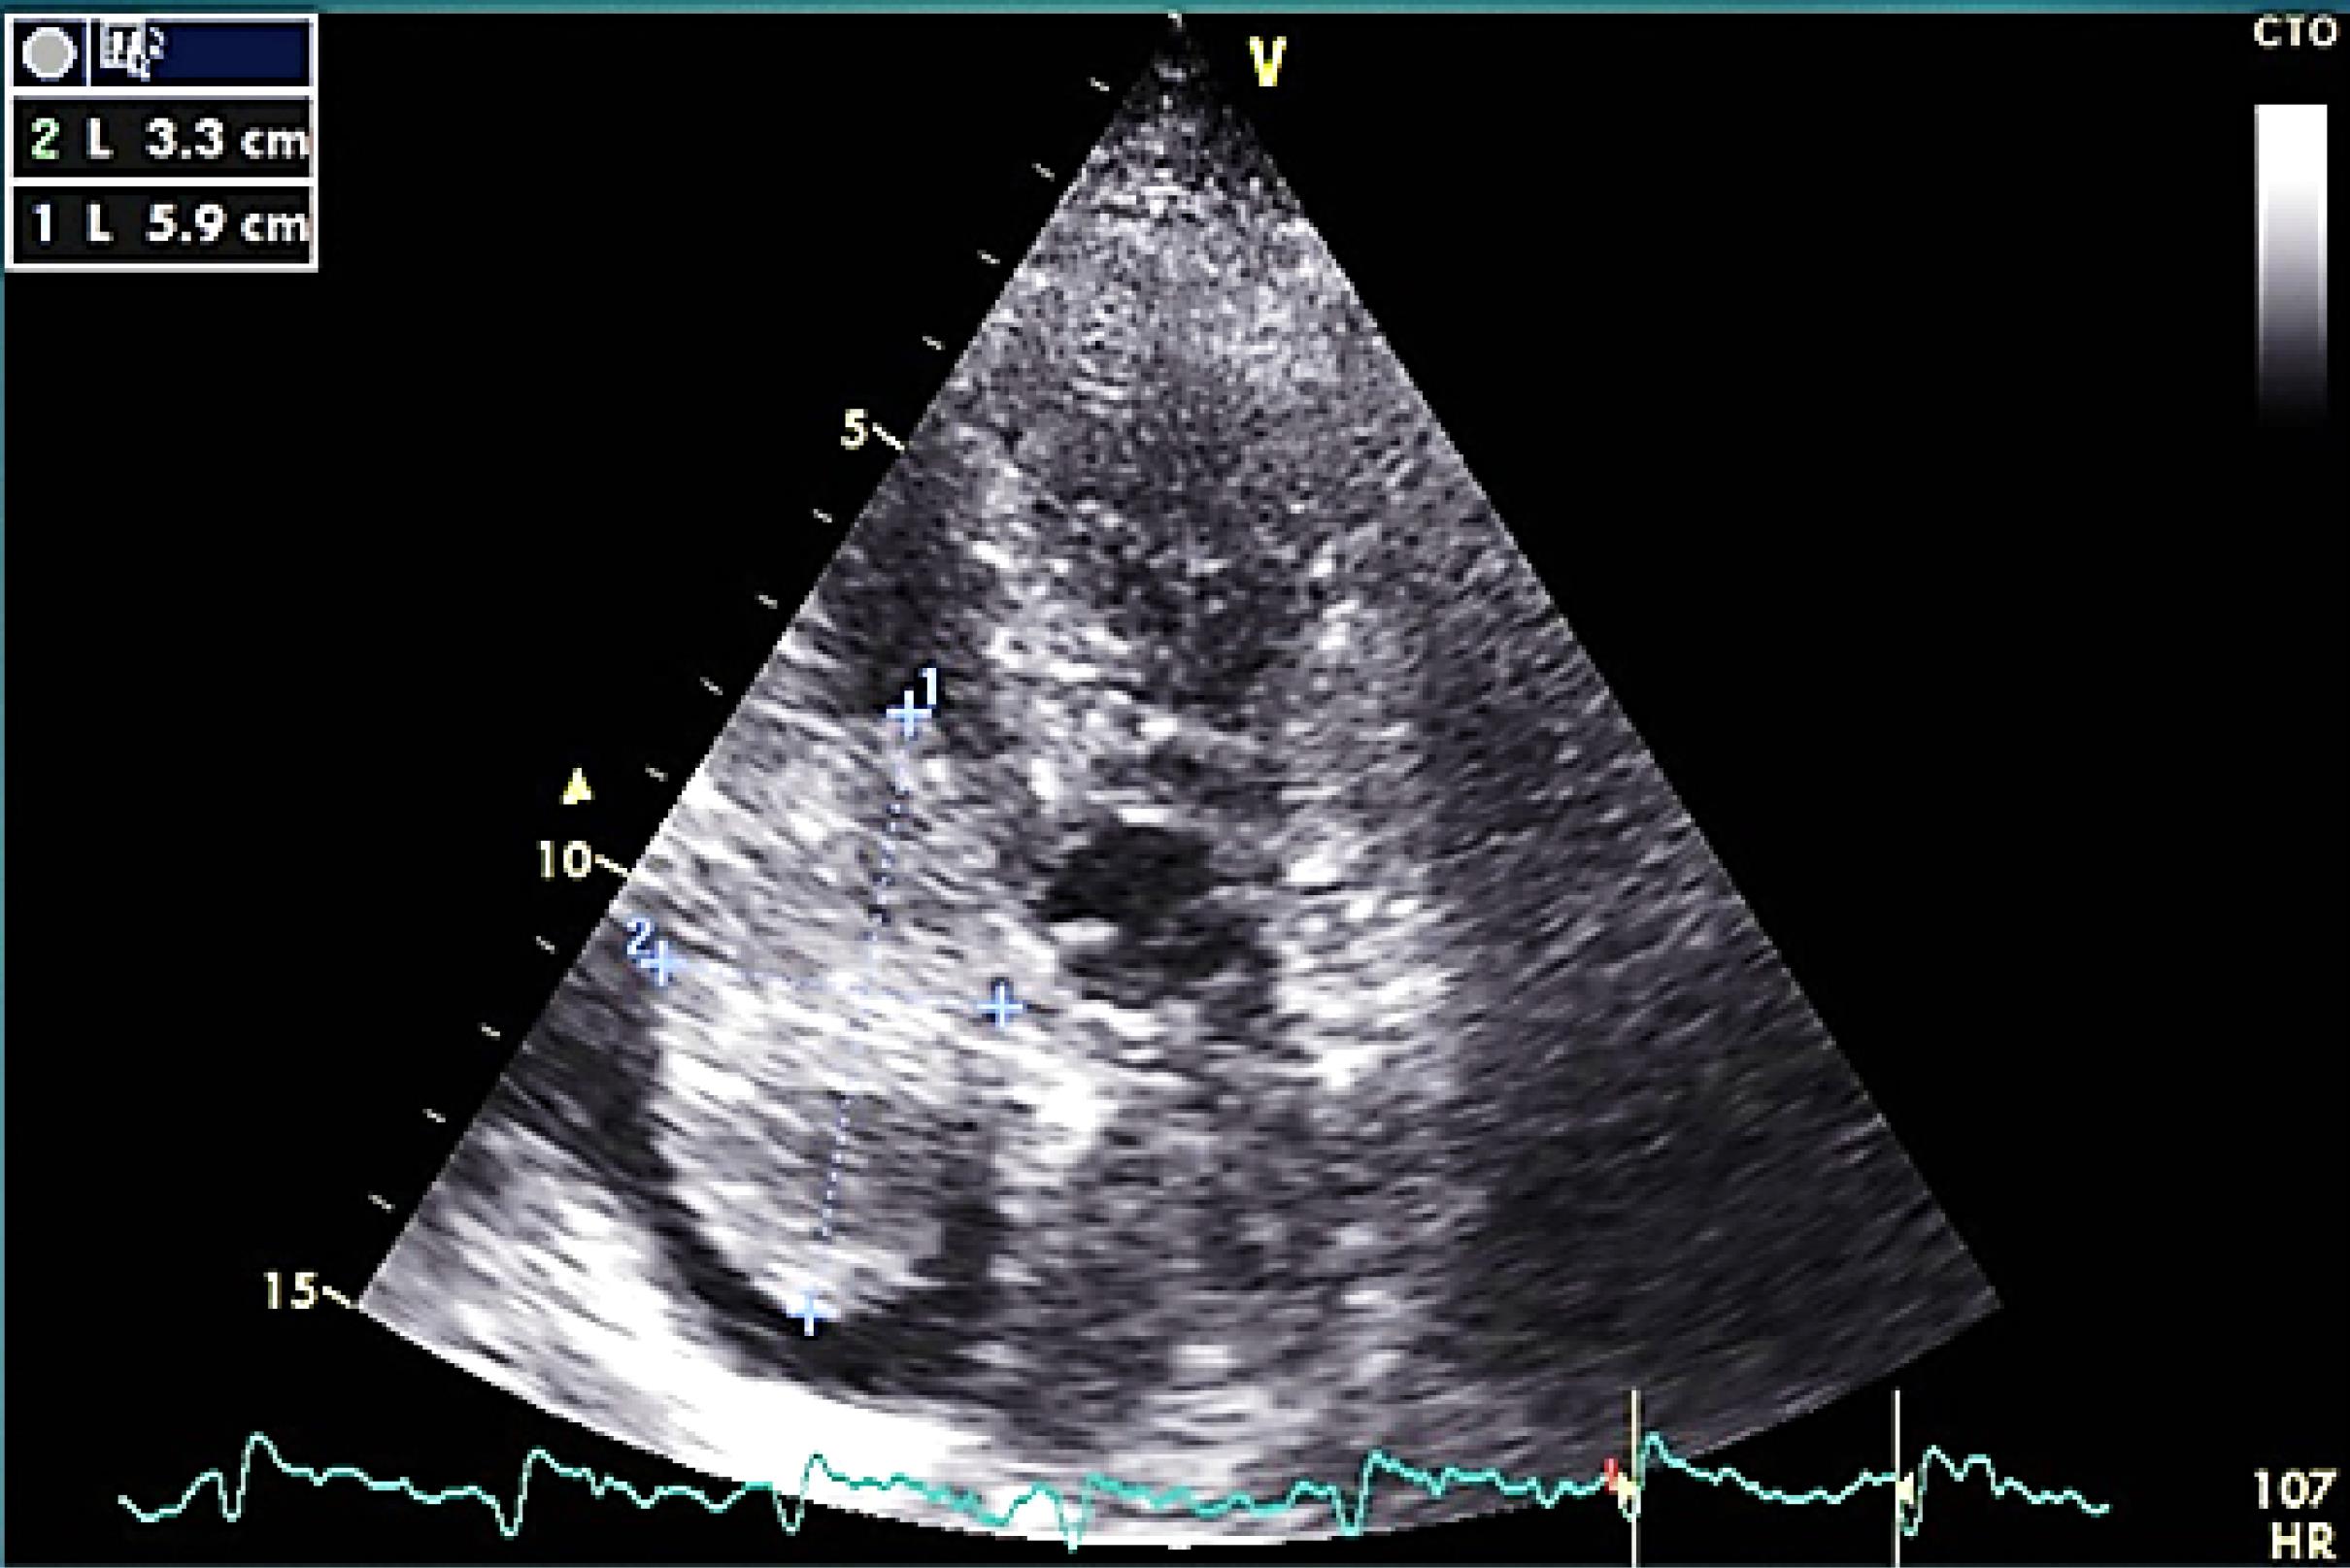

The mass was none homogeneous and several filamentous apparatus was detectable on mass’s surface on echo. In cardiac cycle intermittent protrusion of mass into the TV and dynamic TV stenosis results in cyclic IVC dilation (Figure 2).

Figure 2.

cyclic IVC dilation (because of outflow obstruction) during inspiration (left) and expiration (right)

This was an important sign to confirm the correlation of LOC and this large mass.